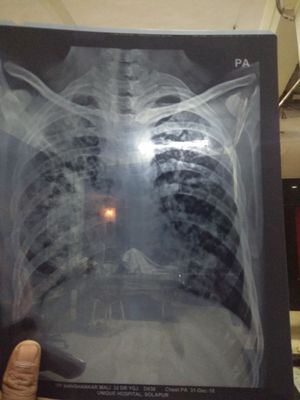

? Tubercular etiology

Chestxray

Chest X-ray in TB